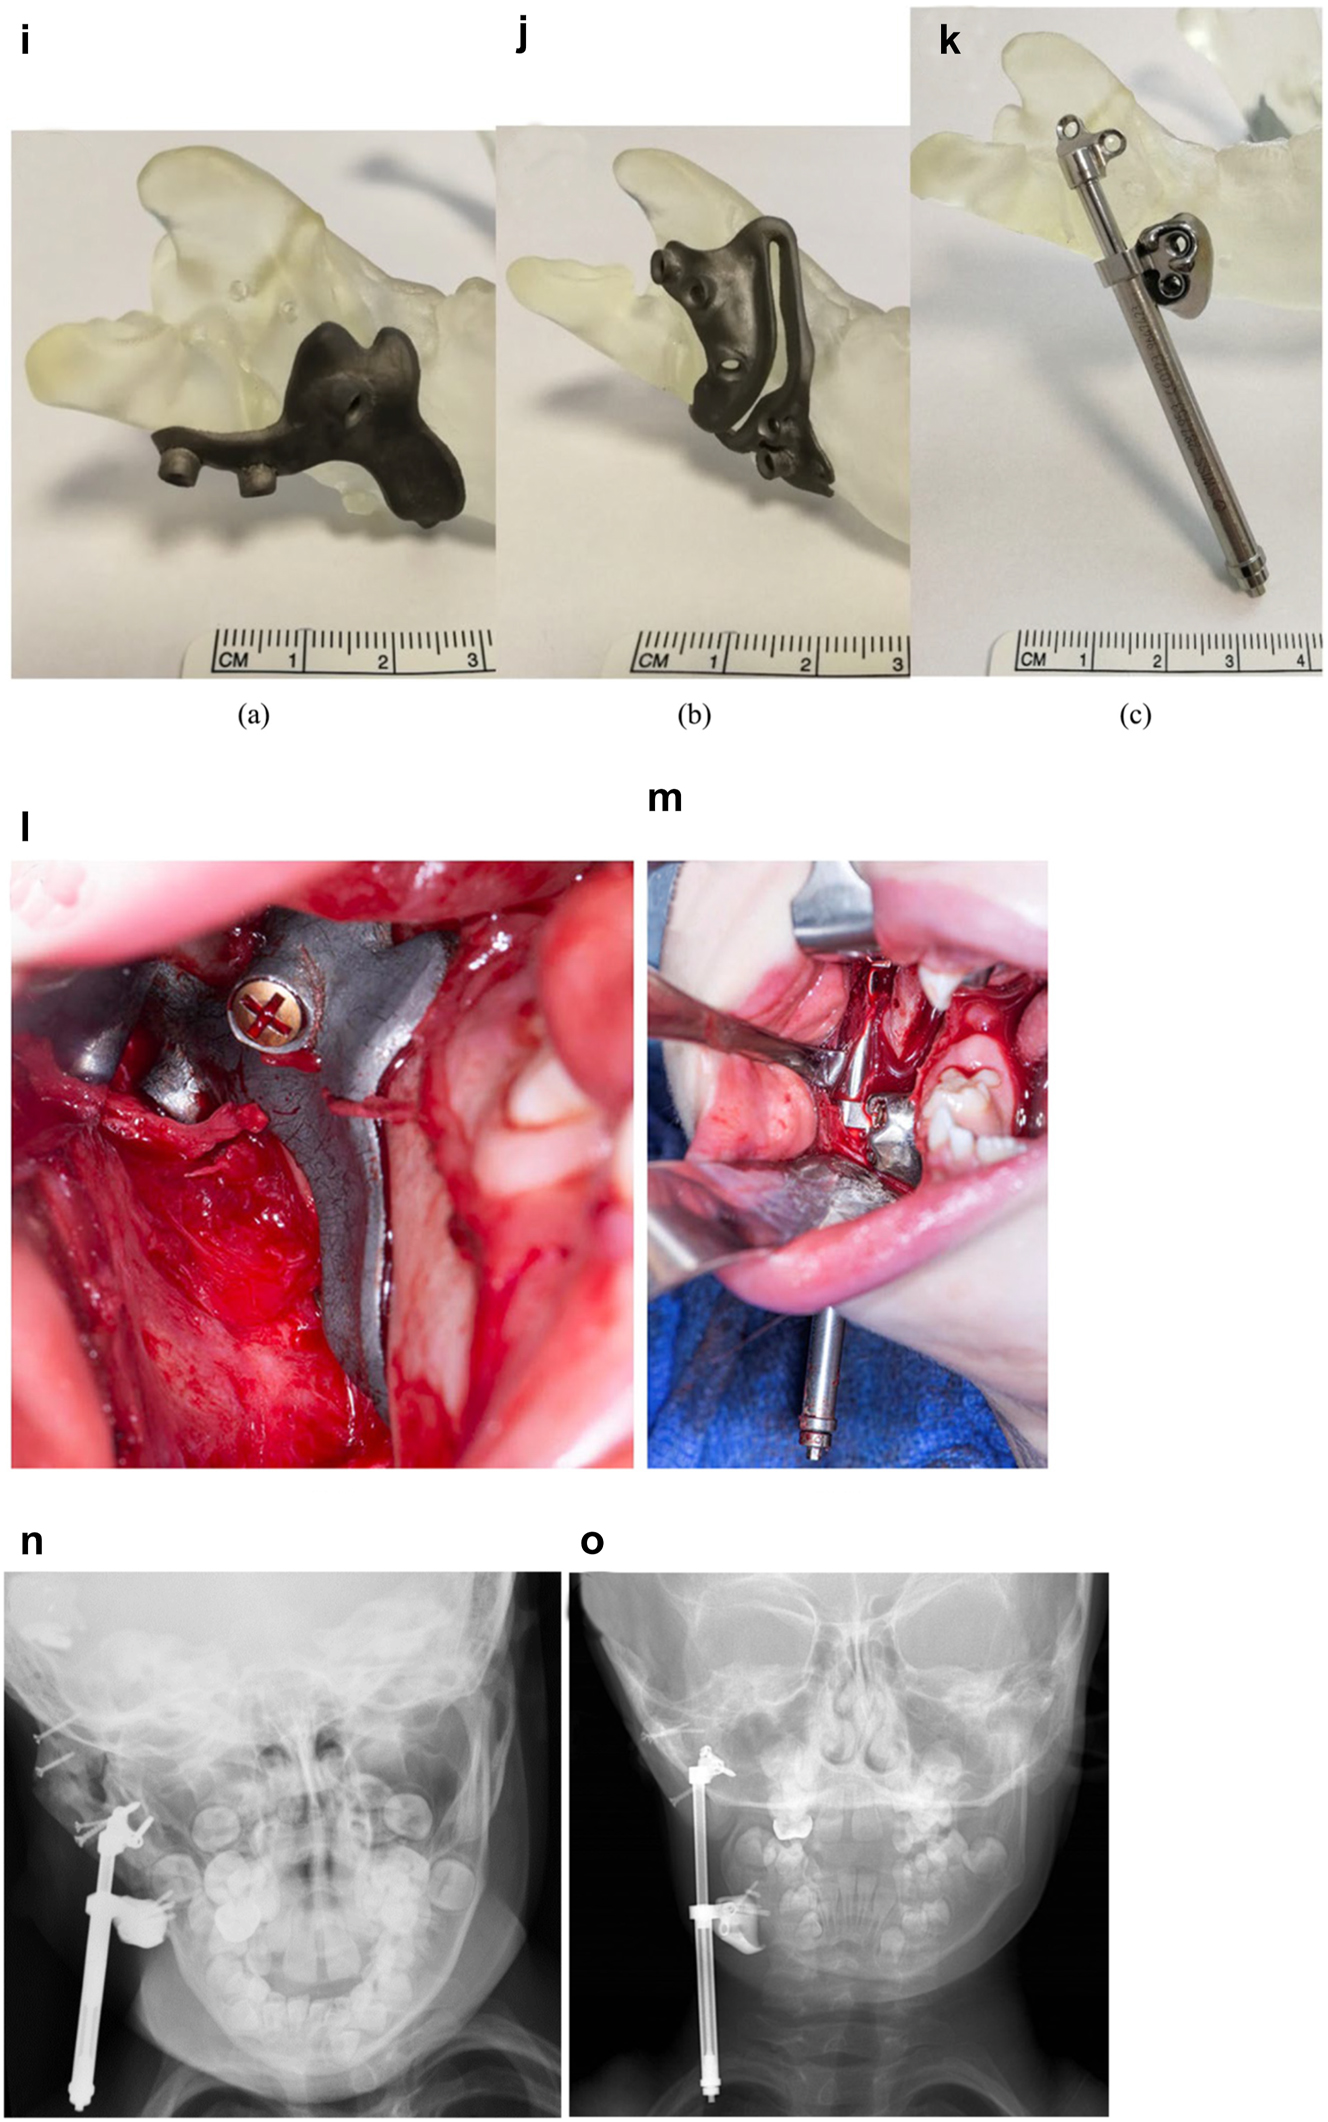

Virtual planning for distraction osteogenesis for ramus lengthening when the lateral ramus contour of the mandible is unfavourable

The principle of using distraction osteogenesis for vertical lengthening of the mandibular ramus is the same whether the patient has had mandibular construction (PK III and IIb cases), or was originally IIa as shown above (Figures 9 and 10). The principle is the same, but the practise may be a little different.

Figure 11:

Planning for DO to vertically lengthen the mandibular ramus when the ramus is deficient laterally. (a and b) The vector problem in this reconstructed case. (c–e) The planned solution correcting the distraction vector to vertical with a spacer. (f–h) The virtual guides.

Planning for DO to vertically lengthen the mandibular ramus when the ramus is deficient laterally. (i–k) The 3D printed guides, spacer and distractor. (l and m) During surgery. (n and o) PA radiographs of the start and end points of distraction.

In previously constructed cases, we carry out the distraction itself within the original part of the mandible (see Figure 20g), not in the consolidated rib graft, as the original part of the mandible to which the previous rib was attached is likely to be more robust. Also it is usually necessary in such cases to remove some metalwork (usually screws) in the planning process and at surgery. The morphology of the lateral mandible on the affected side may be unfavourable preventing a vertical distraction. We have developed a method to address that [23] which we describe below (Figure 11) in a PK IIb case which had been constructed by us previously with a costo-chondral graft.